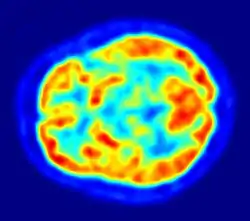

Computer representation of false-color image of a cross section of human brain, based on scintillography in Positron-Emission Tomography

Scintillography is an imaging method of nuclear events provoked by collisions or charged current interactions among nuclear particles or ionizing radiation and atoms which result in a brief, localised pulse of electromagnetic radiation, usually in the visible light range (Cherenkov radiation). This pulse (scintillation) is usually detected and amplified by a photomultiplier or charged coupled device elements, and its resulting electrical waveform is processed by computers to provide two- and three-dimensional images of a subject or region of interest.

Another extensive use of scintillography is in medical imaging techniques which use gamma ray detectors called gamma cameras. Detectors coated with materials which scintillate when subjected to gamma rays are scanned with optical photon detectors and scintillation counters. The subjects are injected with special radionuclides which irradiate in the gamma range inside the region of interest, such as the heart or the brain. A special type of gamma camera is the SPECT (Single Photon Emission Computed Tomography). Another medical scintillography technique, the Positron-emission tomography (PET), which uses the scintillations provoked by electron-positron annihilation phenomena.